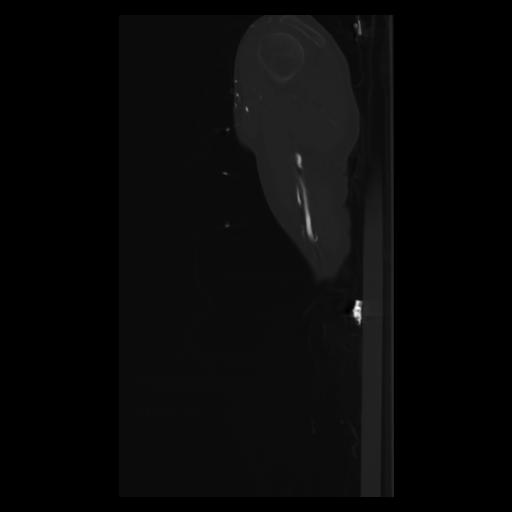

30 CUERPO,CE,Sagittal,3.000,CUERPO,Sagittal,